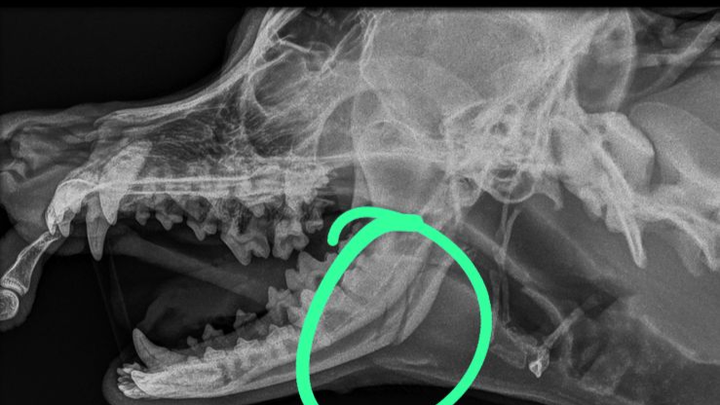

I’m writing with a broken heart and a desperate plea for help. Two days ago, my beloved dogs Coco and Burrito were brutally attacked by several other dogs, leaving them with severe injuries. They have multiple bite wounds and Coco has suffered a broken jaw, which requires immediate surgery to prevent infection and further complications. Without treatment, he could face lifelong issues with eating, drinking, and his overall health. I am deeply worried, but the surgery required to save him is beyond my financial means.

Emergency vet visit for Coco, cranial X-ray, consult with orthopaedic surgeon, surgery, antibiotics, pain management, then whatever ongoing. Care he will need for his recovery